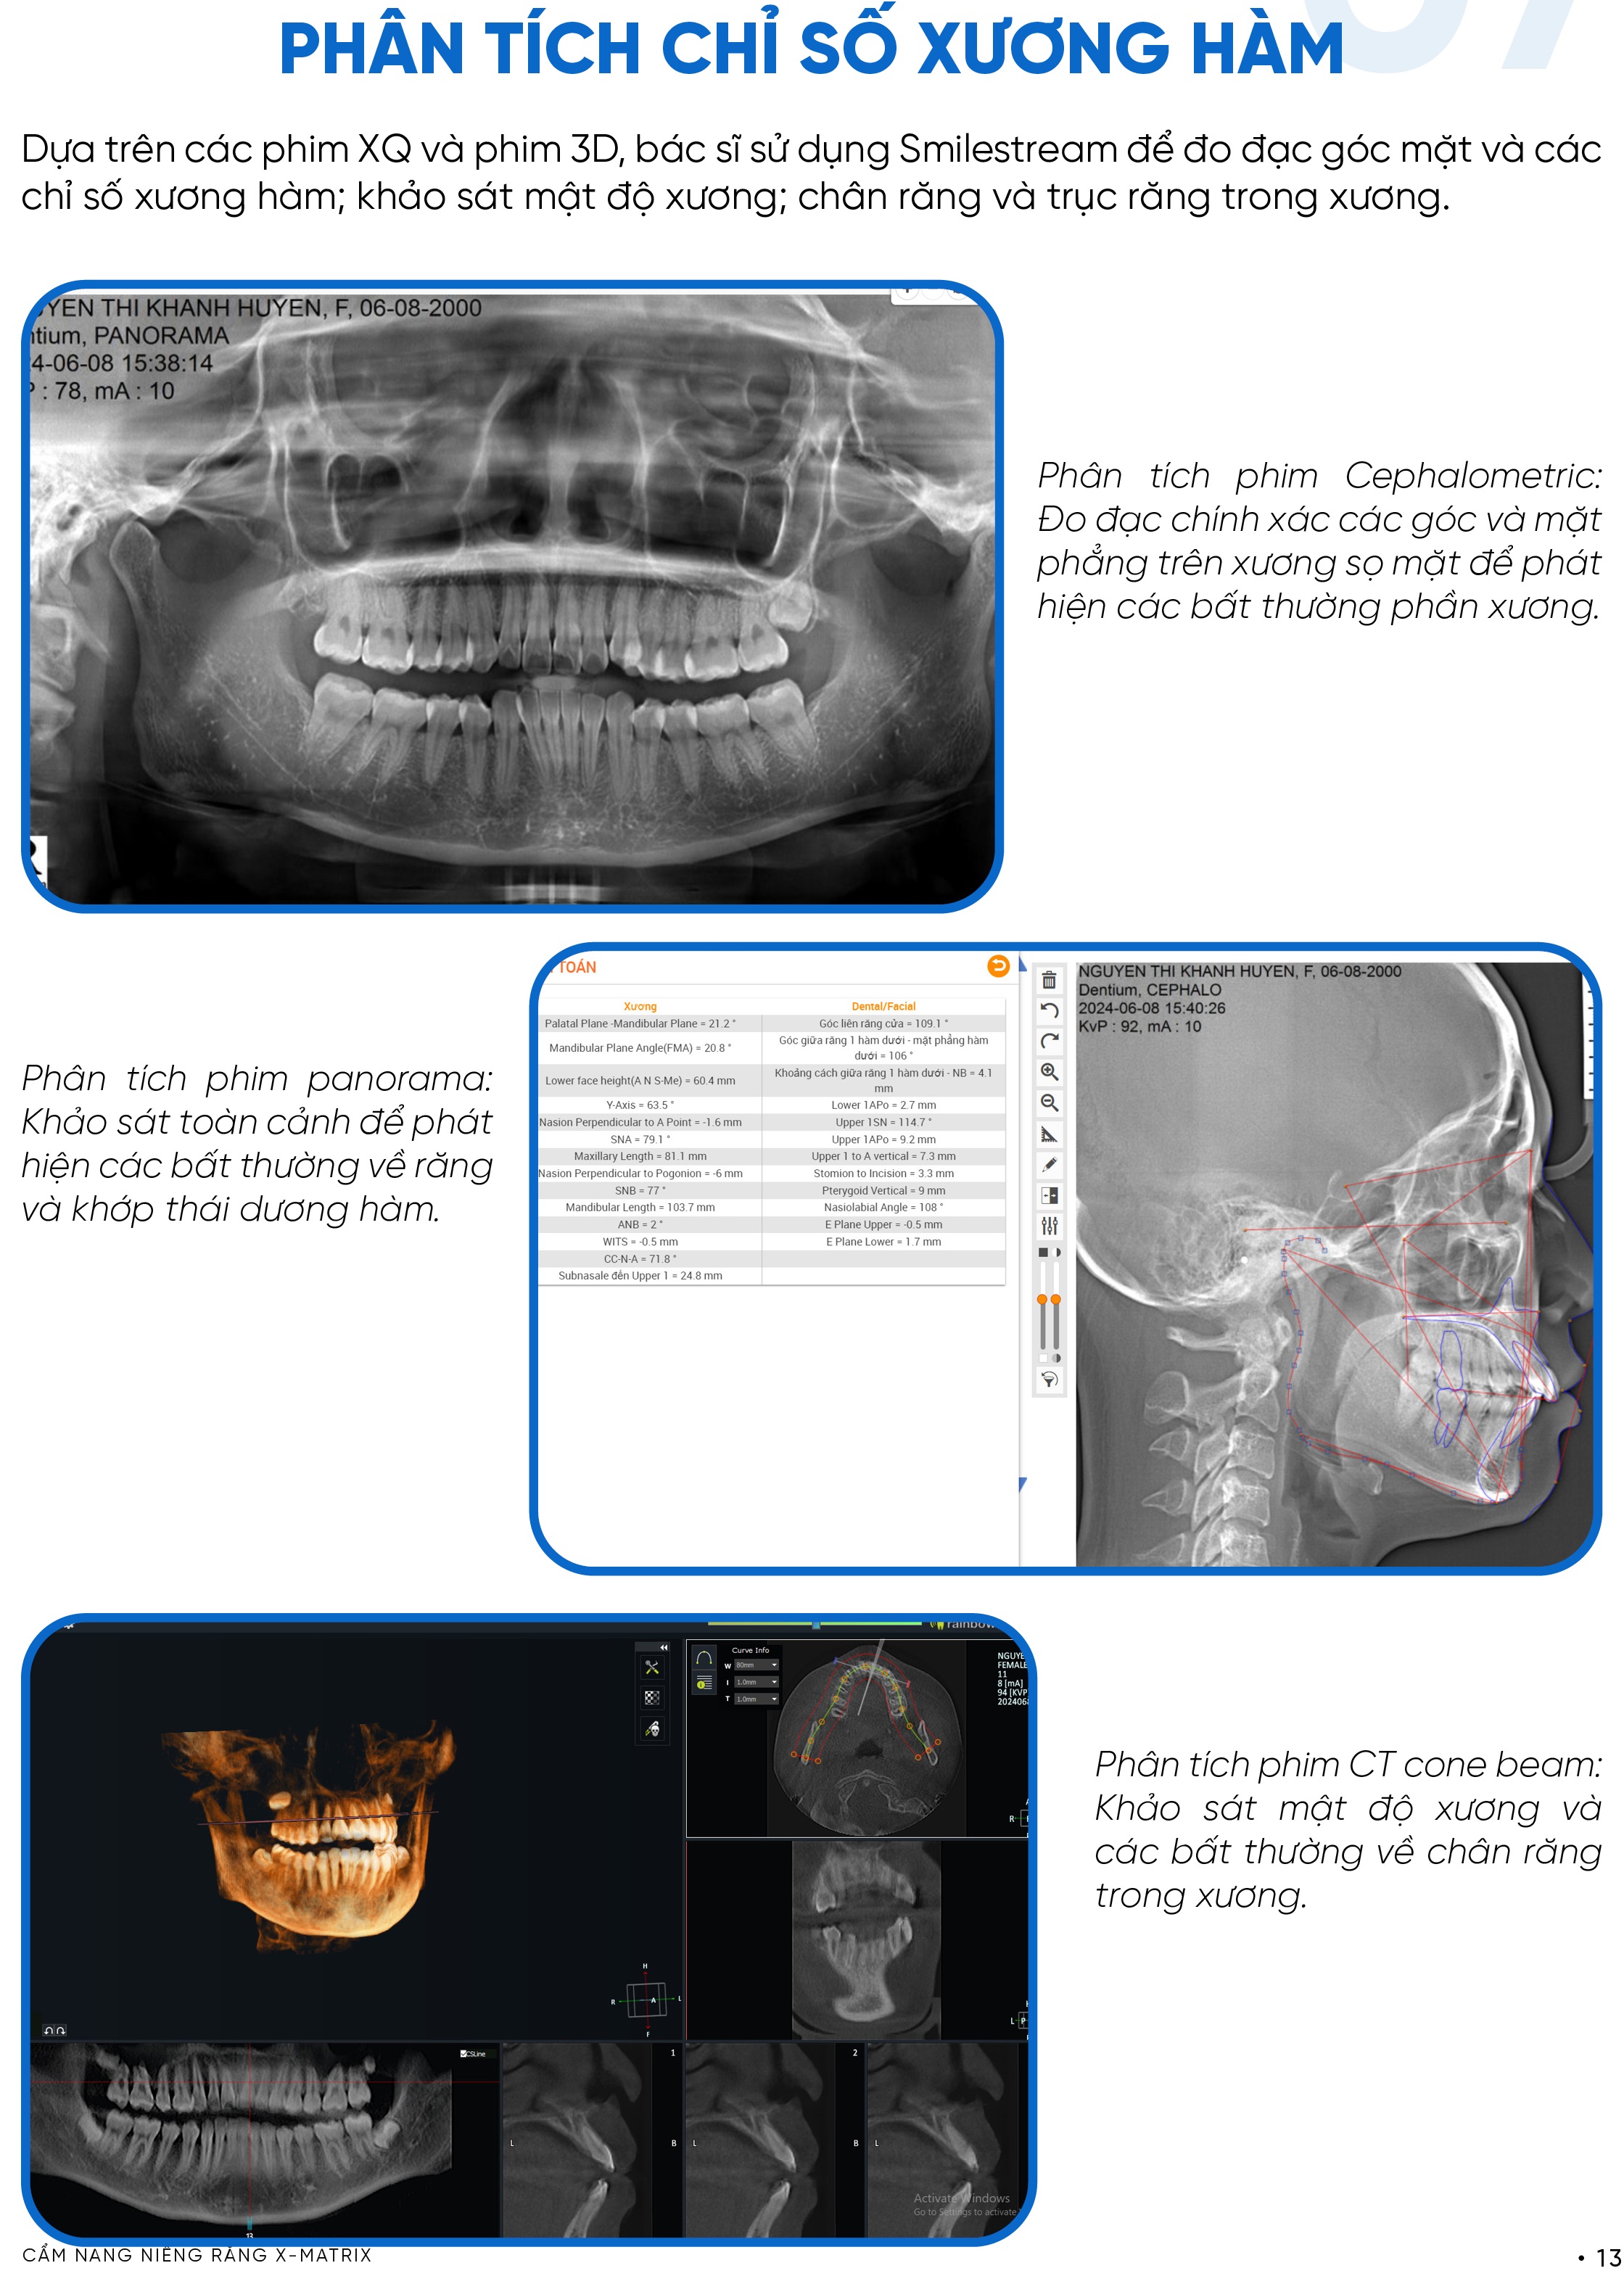

Khách hàng được chụp đầy đủ các loại phim cần thiết để khảo sát cấu trúc xương hàm và chân răng, bao gồm phim sọ nghiêng, phim toàn cảnh và phim CT 3D. Đây là bước bắt buộc để đánh giá chính xác tương quan xương và phát hiện các bất thường tiềm ẩn.

Trong niềng răng X-Matrix, các dữ liệu này được số hóa và tích hợp trực tiếp vào hệ thống phân tích, giúp bác sĩ không chỉ “nhìn” mà còn “đo và kiểm chứng”.